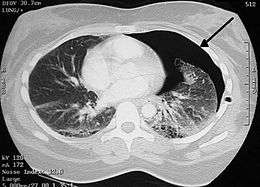

A large right-sided spontaneous pneumothorax (left in the image). An arrow indicates the edge of the collapsed lung

Image from a computed tomography (CT) scan of the chest. On the right (left side of the patient) there is a black area suggesting free air inside the chest

CT scan of the chest showing a pneumothorax on the person's left side (right side on the image). A chest tube is in place (small black mark on the right side of the image), the air-filled pleural cavity (black) and ribs (white) can be seen. The heart can be seen in the center.

Computed tomography

CT with the identification of underlying lung lesion: an apical bulla on the right side.

Computed tomography (CT, or "CAT scan") is not necessary for the diagnosis of pneumothorax, but it can be useful in particular situations. In some lung diseases, especially emphysema, it is possible for abnormal lung areas such as bullae (large air-filled sacs) to have the same appearance as a pneumothorax on chest X-ray, and it may not be safe to apply any treatment before the distinction is made and before the exact location and size of the pneumothorax is determined.[13] In trauma, where it may not be possible to perform an upright film, chest radiography may miss up to a third of pneumothoraces, while CT remains very sensitive.[16]

A further use of CT is in the identification of underlying lung lesions. In presumed primary pneumothorax, it may help to identify blebs or cystic lesions (in anticipation of treatment, see below), and in secondary pneumothorax it can help to identify most of the causes listed above.[13][17]